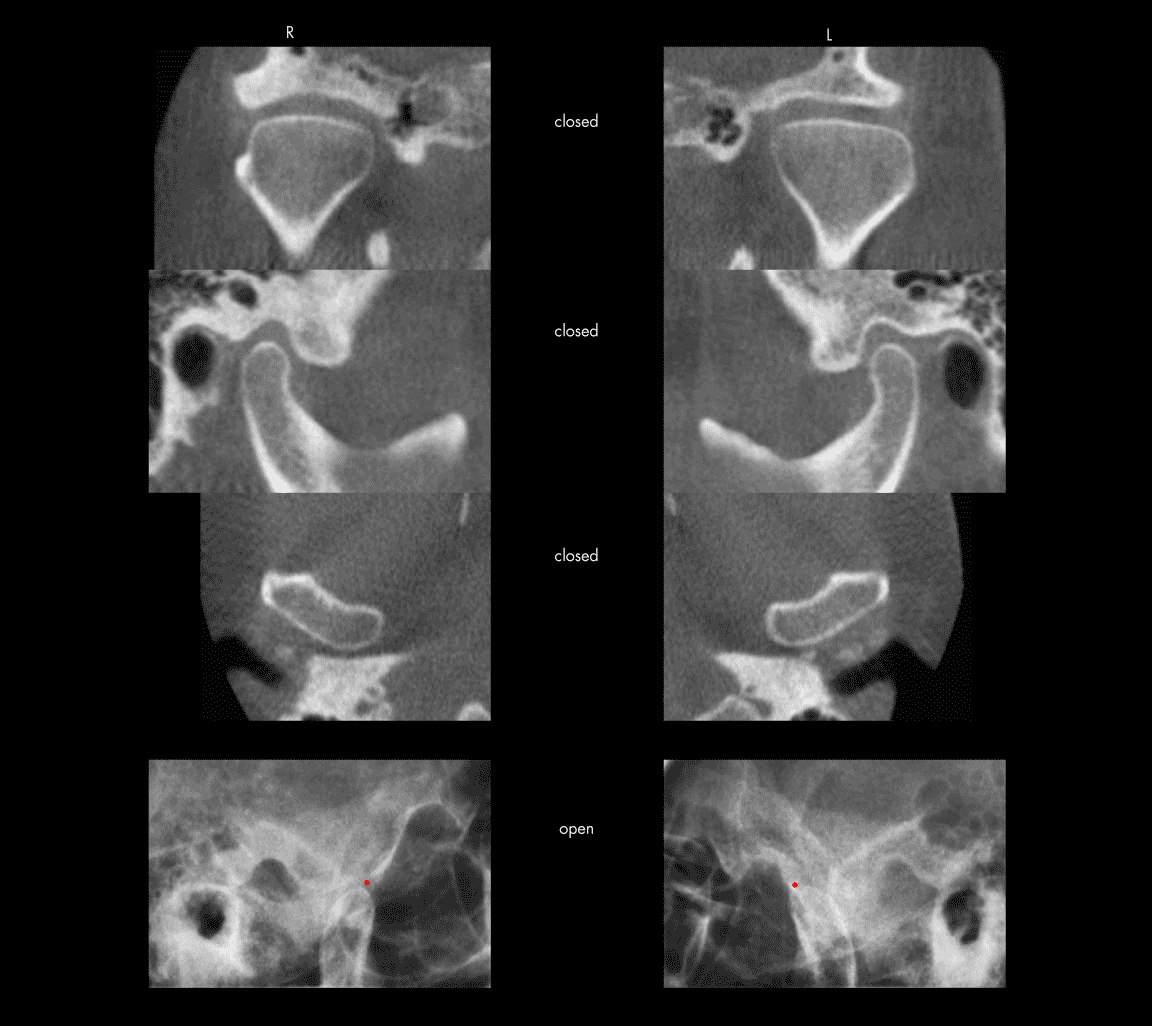

Osteoarthritis